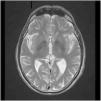

El síndrome de Diógenes constituye un reto para los clínicos. Descrito en adultos mayores, está caracterizado por el abandono extremo del autocuidado, acumulación de objetos inservibles, autonegligencia, aislamiento social y nula conciencia de la enfermedad. Entre un tercio y la mitad cursa con demencias frontotemporales o con algún trastorno mental. Se presenta el caso de un varón de 71 años que ingresa en psiquiatría por alteraciones conductuales. Presenta conducta de acumulación, abandono de higiene, desorganización y pérdida de hábitos. La conducta genera conflictos vecinales y alarma social, por lo que intervienen los servicios sociales. Las pruebas de imagen no aportan hallazgos patológicos significativos. La exploración neuropsicológica indica afectación leve de las áreas prefrontales dorsolaterales, dorsomediales y orbitofrontales. No se objetiva psicopatología aguda. Se interviene multidisciplinarmente, en formato de hospital de día, con supervisión conductual, plan de estructuración del tiempo, promoción de la autonomía y apoyo social. Este caso evidencia la complejidad del proceso diagnóstico y la movilización de recursos sociales, sanitarios y legales dadas las repercusiones en todas las áreas.

Diogenes syndrome is a challenge for clinicians. It is described in older adults. It is characterized by extreme neglect of self-care, accumulation of useless objects, self-neglect, social isolation and no awareness of illness. Between a third and a half of the patients have frontotemporal dementias or a mental disorder. We present the case of a 71-year-old male admitted to psychiatry due to behavioral disorders. He presents hoarding behavior, neglect of hygiene, disorganization and loss of habits. The behavior generates neighborhood conflicts and social alarm, for which social services intervene. Neuroimaging studies do not provide significant pathologic findings. Neuropsychological examination showed mild involvement of dorsolateral, dorsomedial, and orbitofrontal prefrontal areas. No acute psychopathology was observed. Multidisciplinary intervention is performed in a day hospital, with behavioral supervision, time structuring plan, promotion of autonomy and social support. This case shows the complexity of the diagnostic process and the mobilization of social, health and legal resources given the repercussions in all areas.